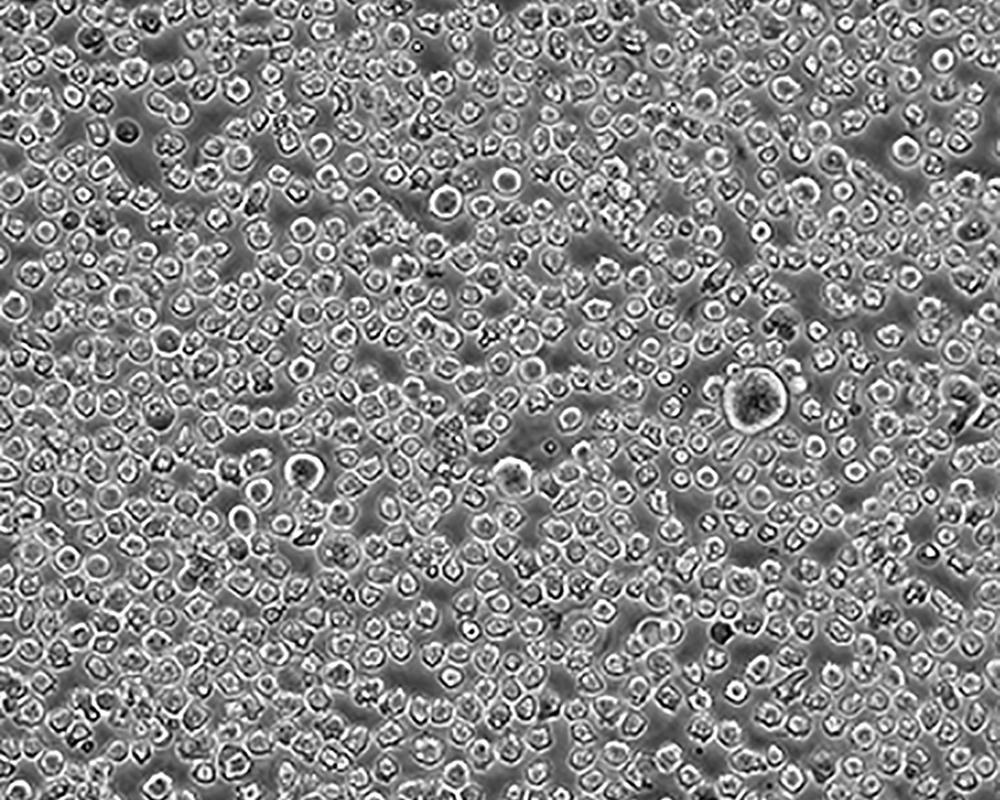

K-562 [K562]細胞

產品名稱 K-562 [K562]細胞

中文名稱 人慢性髓原白血病細胞

組織來源 慢性髓細胞白血病;女性

生長特性 suspension

形態(tài)特征 lymphoblast

細胞描述 The cell population has been characterized as highly undifferentiated and of the granulocytic series. Studies conducted by Anderson, et al. , on the surface membrane properties led to the conclusion that the K-562 was a human erythroleukemia line. K-562 blasts are multipotential, hematopoietic malignant cells that spontaneously differentiate into recognizable progenitors of the erythrocytic, granulocytic and monocytic series. The effect of inducers on sublines derived from the original K-562 cell line have been reviewed by Koeffler and Golde. Karyological studies on various K- 562 sublines have been classified into three groups(A,B,C) by Dimery, et al. The strain obtained by the ATCC most closely resembles the B population. Occurrence of the Philadelphia chromosome, however, was of much lower frequency; none detected in 15 metaphases examined. The line is EBNA negative.